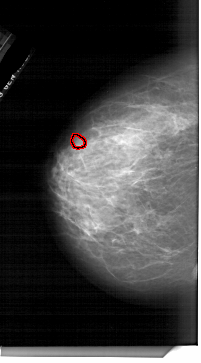

A_1761_1.RIGHT_CC

RIGHT_CC LINES 6256 PIXELS_PER_LINE 3601 BITS_PER_PIXEL 12 RESOLUTION 43.5 NON_OVERLAY

FILE: A_1761_1.LEFT_MLO.OVERLAY

TOTAL_ABNORMALITIES 1

ABNORMALITY 1

LESION_TYPE MASS SHAPE OVAL MARGINS ILL_DEFINED

ASSESSMENT 4

SUBTLETY 3

PATHOLOGY BENIGN

TOTAL_OUTLINES 1